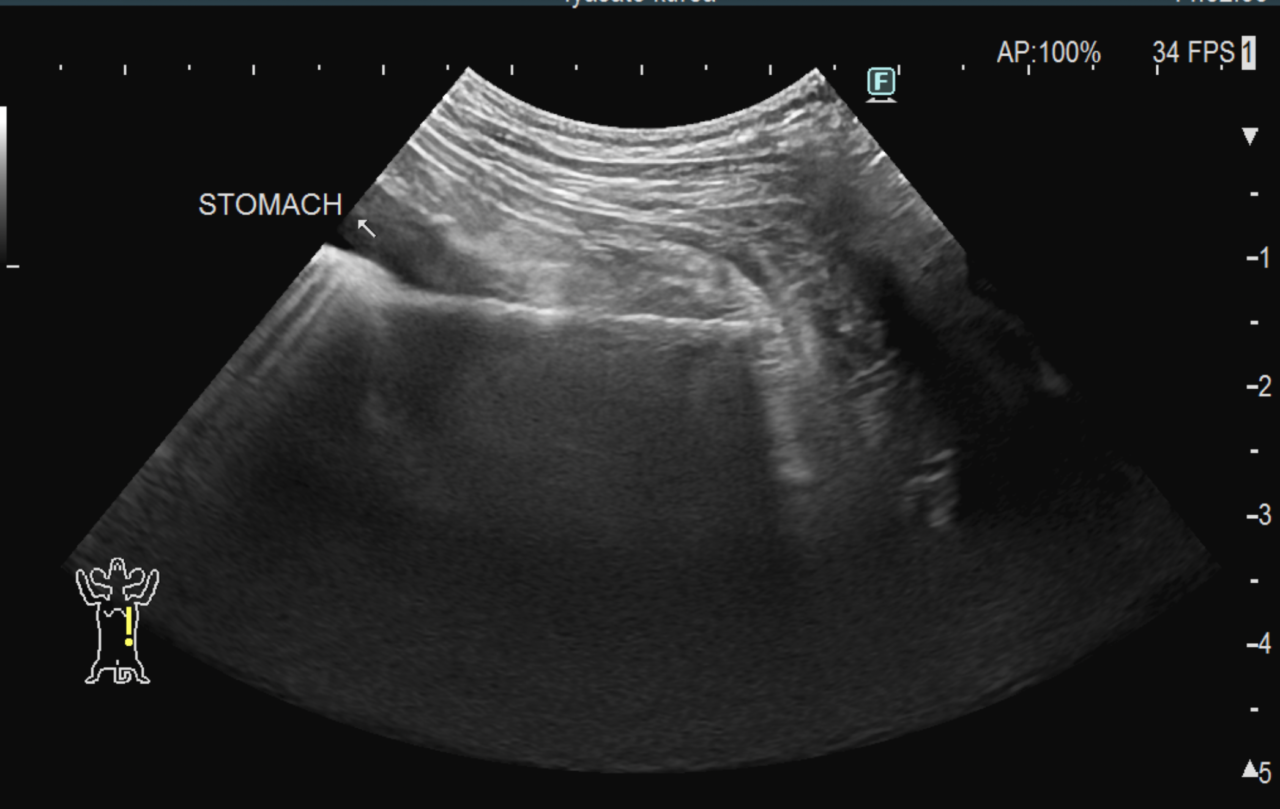

1週間前に団子を串ごと誤飲した可能性があるワンコが急にぐったりしているとのこと。すぐに地元の救急病院を受診すると異物による胃穿孔が疑われました。外科的な摘出と腹膜炎によるクリティカルケアが予想されたため紹介来院しました。開腹後、竹串による胃穿孔が確定されました。腹膜炎も同時に起こっています。穿孔創を封鎖し、腹腔洗浄とドレインの設置を行いました。幸いにも48時間後に食欲が出て退院となりました。愛犬が竹串を誤飲してしまったら、命に関わる事態に発展する可能性もあるため、早めに内視鏡による摘出をお勧めします。このような異物を発見するためにはエックス線よりも超音波検査が非常に有効です。